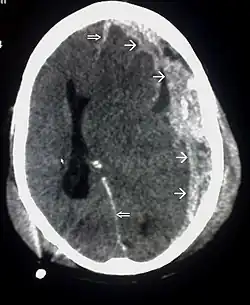

![]() | |

| CT scan showing cerebral contusions, hemorrhage within the hemispheres, and subdural hematoma. There is also displaced skull fracture of left transverse parietal and temporal bones.[2] | |